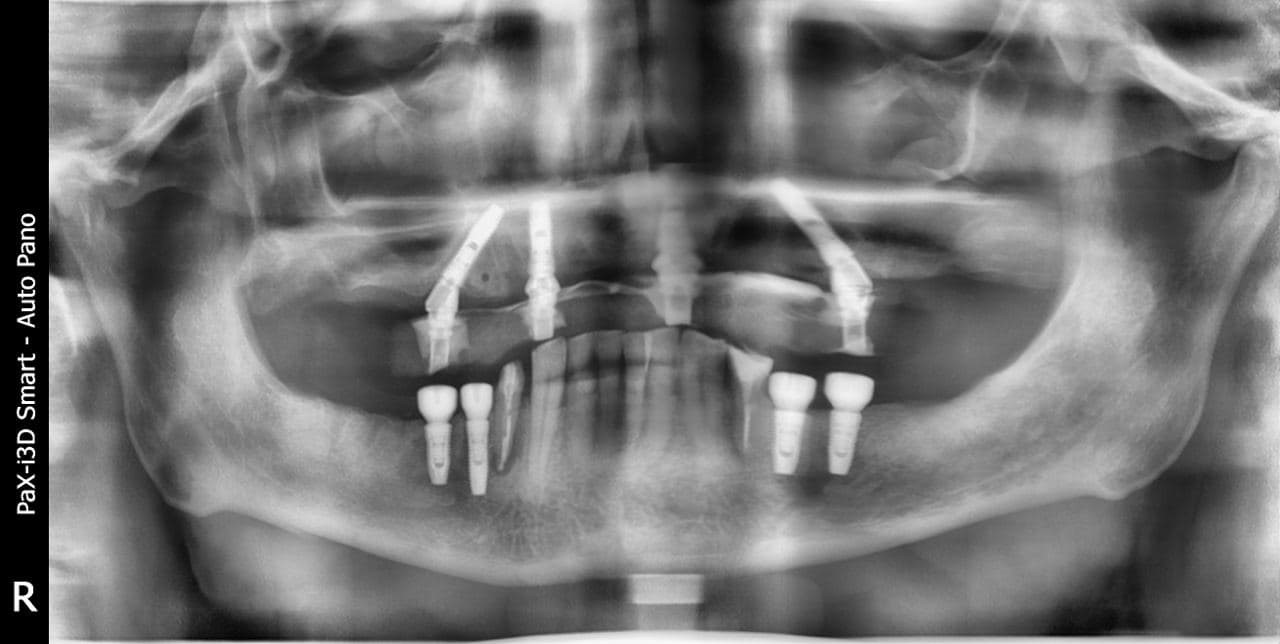

Расскажу просто эпический случай мужика, который пострадал от российской медицины далеко не один раз. Итак, на момент приёма у нас пациенту 75 лет. Он несколько десятков лет наблюдался у своего постоянного стоматолога, но его привело в некоторое сомнение то, что последнее, что он ему сделал, отвалилось через неделю. И мужчина решил получить второе мнение. Мы и были вторым мнением. На диагностике мы увидели, что каналы корней вылечены плохо и давно, перелечивать их смысла уже нет, потому что ткани над десной тоже почти нигде нет. И из этих фрагментов зубов показываются штифты, то есть культевые вкладки потеряли герметичность. Вторичный кариес дополняет картину постапокалипсиса.

1. Пациент приходит на консультацию. Точнее, его приводит сын, потому что, похоже, что-то пошло не так с прошлым врачом. Это что-то вообще-то можно заметить невооружённым взглядом, но сын далеко не дантист. Но в целом он способен понять, что пеньки зубов с торчащими из них странными штуками — это не очень здоровая ситуация. В руках у пациента — коронки, которые отвалились буквально недавно. Итого восемь пеньков на верхней челюсти и несколько сохранившихся зубов на нижней. Визуально зубов нет, внутри кости есть разрушенные корни, сверху — культяшечки, на которые пытались приклеить конструкцию.

2. Мы сканируем ротовую полость 3D-сканером (это панорамная камера с координатной привязкой), делаем КТ, получаем полную картину снаружи и внутри. Видим описанную выше ситуацию.